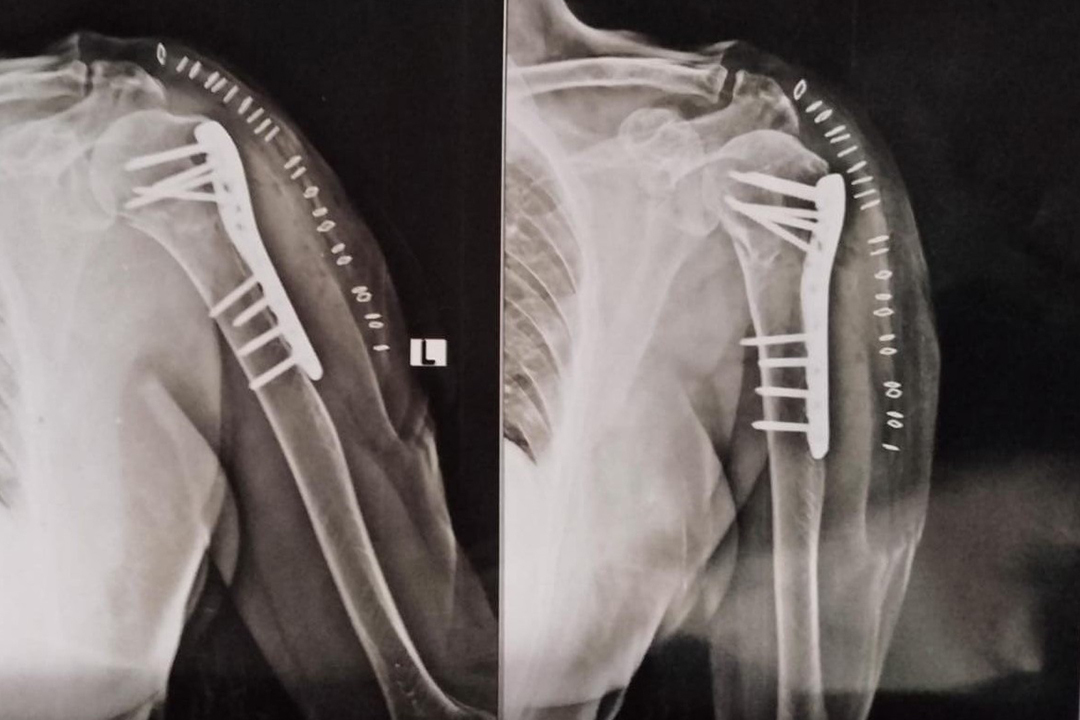

Radiographic Evaluation

Post-operative X-ray: Anatomical reduction with stable fixation using PHILOS plate